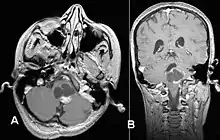

Usually – depending on the interview of the patient and after a clinical exam which includes a neurological exam and an ophthalmological exam – a CT scan and/or an MRI scan will be performed to confirm the presence of a tumor. They are usually easily distinguishable from normal brain structures using these imaging techniques. A special dye may be injected into a vein before these scans to provide contrast and make tumors easier to identify. Pilocytic astrocytomas are typically clearly visible on such scans, but it is often difficult to say based on imaging alone what type of tumor is present.

Pilocytic astrocytomas are often cystic tumors, and, if solid, tend to be well-circumscribed.

Under the microscope, the tumor is seen to be composed of bipolar cells with long "hair-like" GFAP-positive processes, giving the designation "pilocytic" (that is, made up of cells that look like fibers when viewed under a microscope[6]). Some pilocytic astrocytomas may be more fibrillary and dense in composition. The presence of Rosenthal fibers,[7] eosinophilic granular bodies, and microcysts can often be seen. Myxoid foci and oligodendroglioma-like cells may also be present, though these are not specific to pilocytic astrocytoma. Long-standing lesions may show hemosiderin-laden macrophages and calcifications.